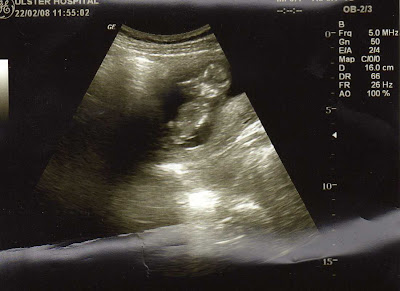

Exciting news in the McCready family. Rebecca is pregnant with our first child. We went to the hospital yesterday for the twelve week scan. Thankfully everything is well with Becca and with wee McCready. I am dumping myself, I mean I can hardly look after myself, the thought that God would trust me to look after a wee baby. Anyway the details at 12 weeks and 3 days are that there is a wee baby, 5.9 cm (that is nearly the same size as me) and God willing should be born on September 1st 2008. Prayers for this next six months would be much appreciated.

Here is the wee monster...